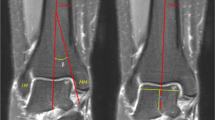

Based on the plain radiographs, 22 patients of the OA group were found to be in stage 3a, 3b, or 4 on the OA side and in stage 1 or less on the opposite non-OA side, according to the Takakura classification10. The numbers of patients classified into each stage were five, eleven, and six, respectively. Thirteen patients of the control group were not diagnosed as having ankle OA on plain radiographs. There were no significant differences between the two groups in age and the sex ratio.

Thirty-five patients (average age, 70.1 years; range, 41 to 88 years; 8 males, 27 females), consisting of an ankle OA group and a control group, were recruited in this study. The ankle OA group included 22 patients (71.1 years; 49 to 88 years; 5 males, 17 females) diagnosed with unilateral varus ankle OA. Varus ankle OA was judged based on a talar medial tilt angle > 4° measured on weight-bearing anterior-posterior radiographs18, and stage > 3a according to the Takakura classification. Patients with ankle OA following fractures of the tibia, ankle, or talus or inflammatory diseases such as rheumatoid and infectious arthritis were excluded. Both secondary ankle OA patients following repetitive ligamentous injuries and primary ankle OA patients with unknown sprain histories were included in the analysis. The Takakura classification10 of the recruited ankle OA patients was independently evaluated by two of the authors, who are foot and ankle orthopedic surgeons with more than 10 years of experience (H.S. and T.K.), and the classification results were completely identical. The control group included 13 patients (68.5 years; 41 to 84 years; 3 males, 10 females) with fresh trauma without involvement of the talus, such as fractures of the tibia, calcaneus, or forefoot. The diagnostic process with interviews confirmed all patients to be free of any foot and ankle pathologies except for the above fresh trauma. The present study was approved by the Institutional Review Board of Tachikawa Hospital (Tokyo, Japan), and informed consent was obtained from all patients. The methods were carried out in accordance with the approved guidelines.